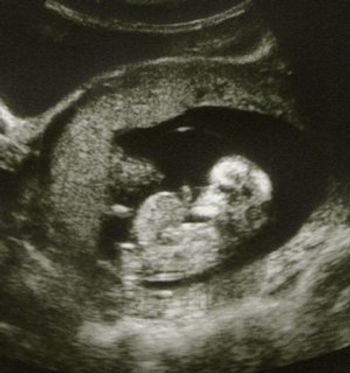

A 29-year-old gravida 10, para 3 (1 term gestation, 1 preterm gestation of twins, 1 stillbirth at 5 months, 2 spontaneous abortions, and 4 elective abortions) presented to the clinic at about 5 weeks’ gestation with abdominal pain and vaginal bleeding. She described the pain as sporadic, mostly on the left side, exacerbated by movement, and resolving with rest, and the bleeding as initially intermittent but then heavier “like a period.”

Implantation in the scar of a previous Cesarean is thought to be the rarest of ectopic pregnancies. With the increasing numbers of Cesareans performed, scar implantation may become more frequent as well. We present an illustrative case.